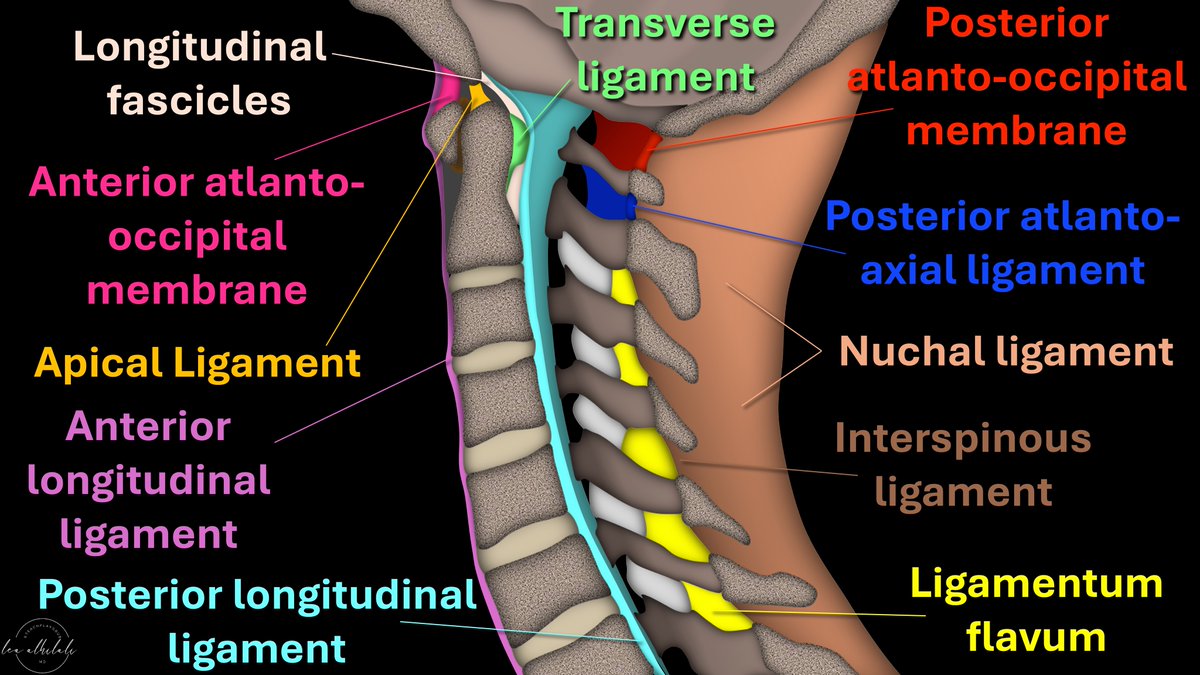

Afraid to stick your neck out when it comes to naming cervical spine ligaments? Know the anterior longitudinal ligament (ALL) \u0026 that's ALL? Is the nuchal ligament a NEW CALL for you?

image size: 1200x675

Do You Have Neck Pain? It Could Be Coming From Your Ligaments - Old Post Physical Therapy